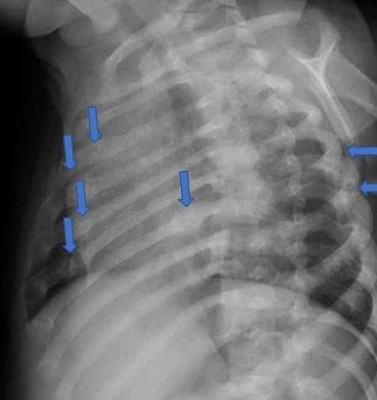

肋骨也断了不少处。

据英国《太阳报》报道,32岁男子建卓札克与22岁妻子柯宾丝卡,在2017年时把年仅4个月大的儿子送到医院,全身是伤。医师检查后认为状况有异,夫妻俩则直呼孩子是被边缘翘起来的地毯绊倒,但医师发现,孩子身上共有28处骨折,而且伤势相当严重,包括手臂、肋骨、膝盖、脚踝等几乎都是全断的状况。医师验伤认为,男婴遭到强大的外力冲击,因此报警处理,建卓札克和柯宾丝卡随后遭到警方逮捕。